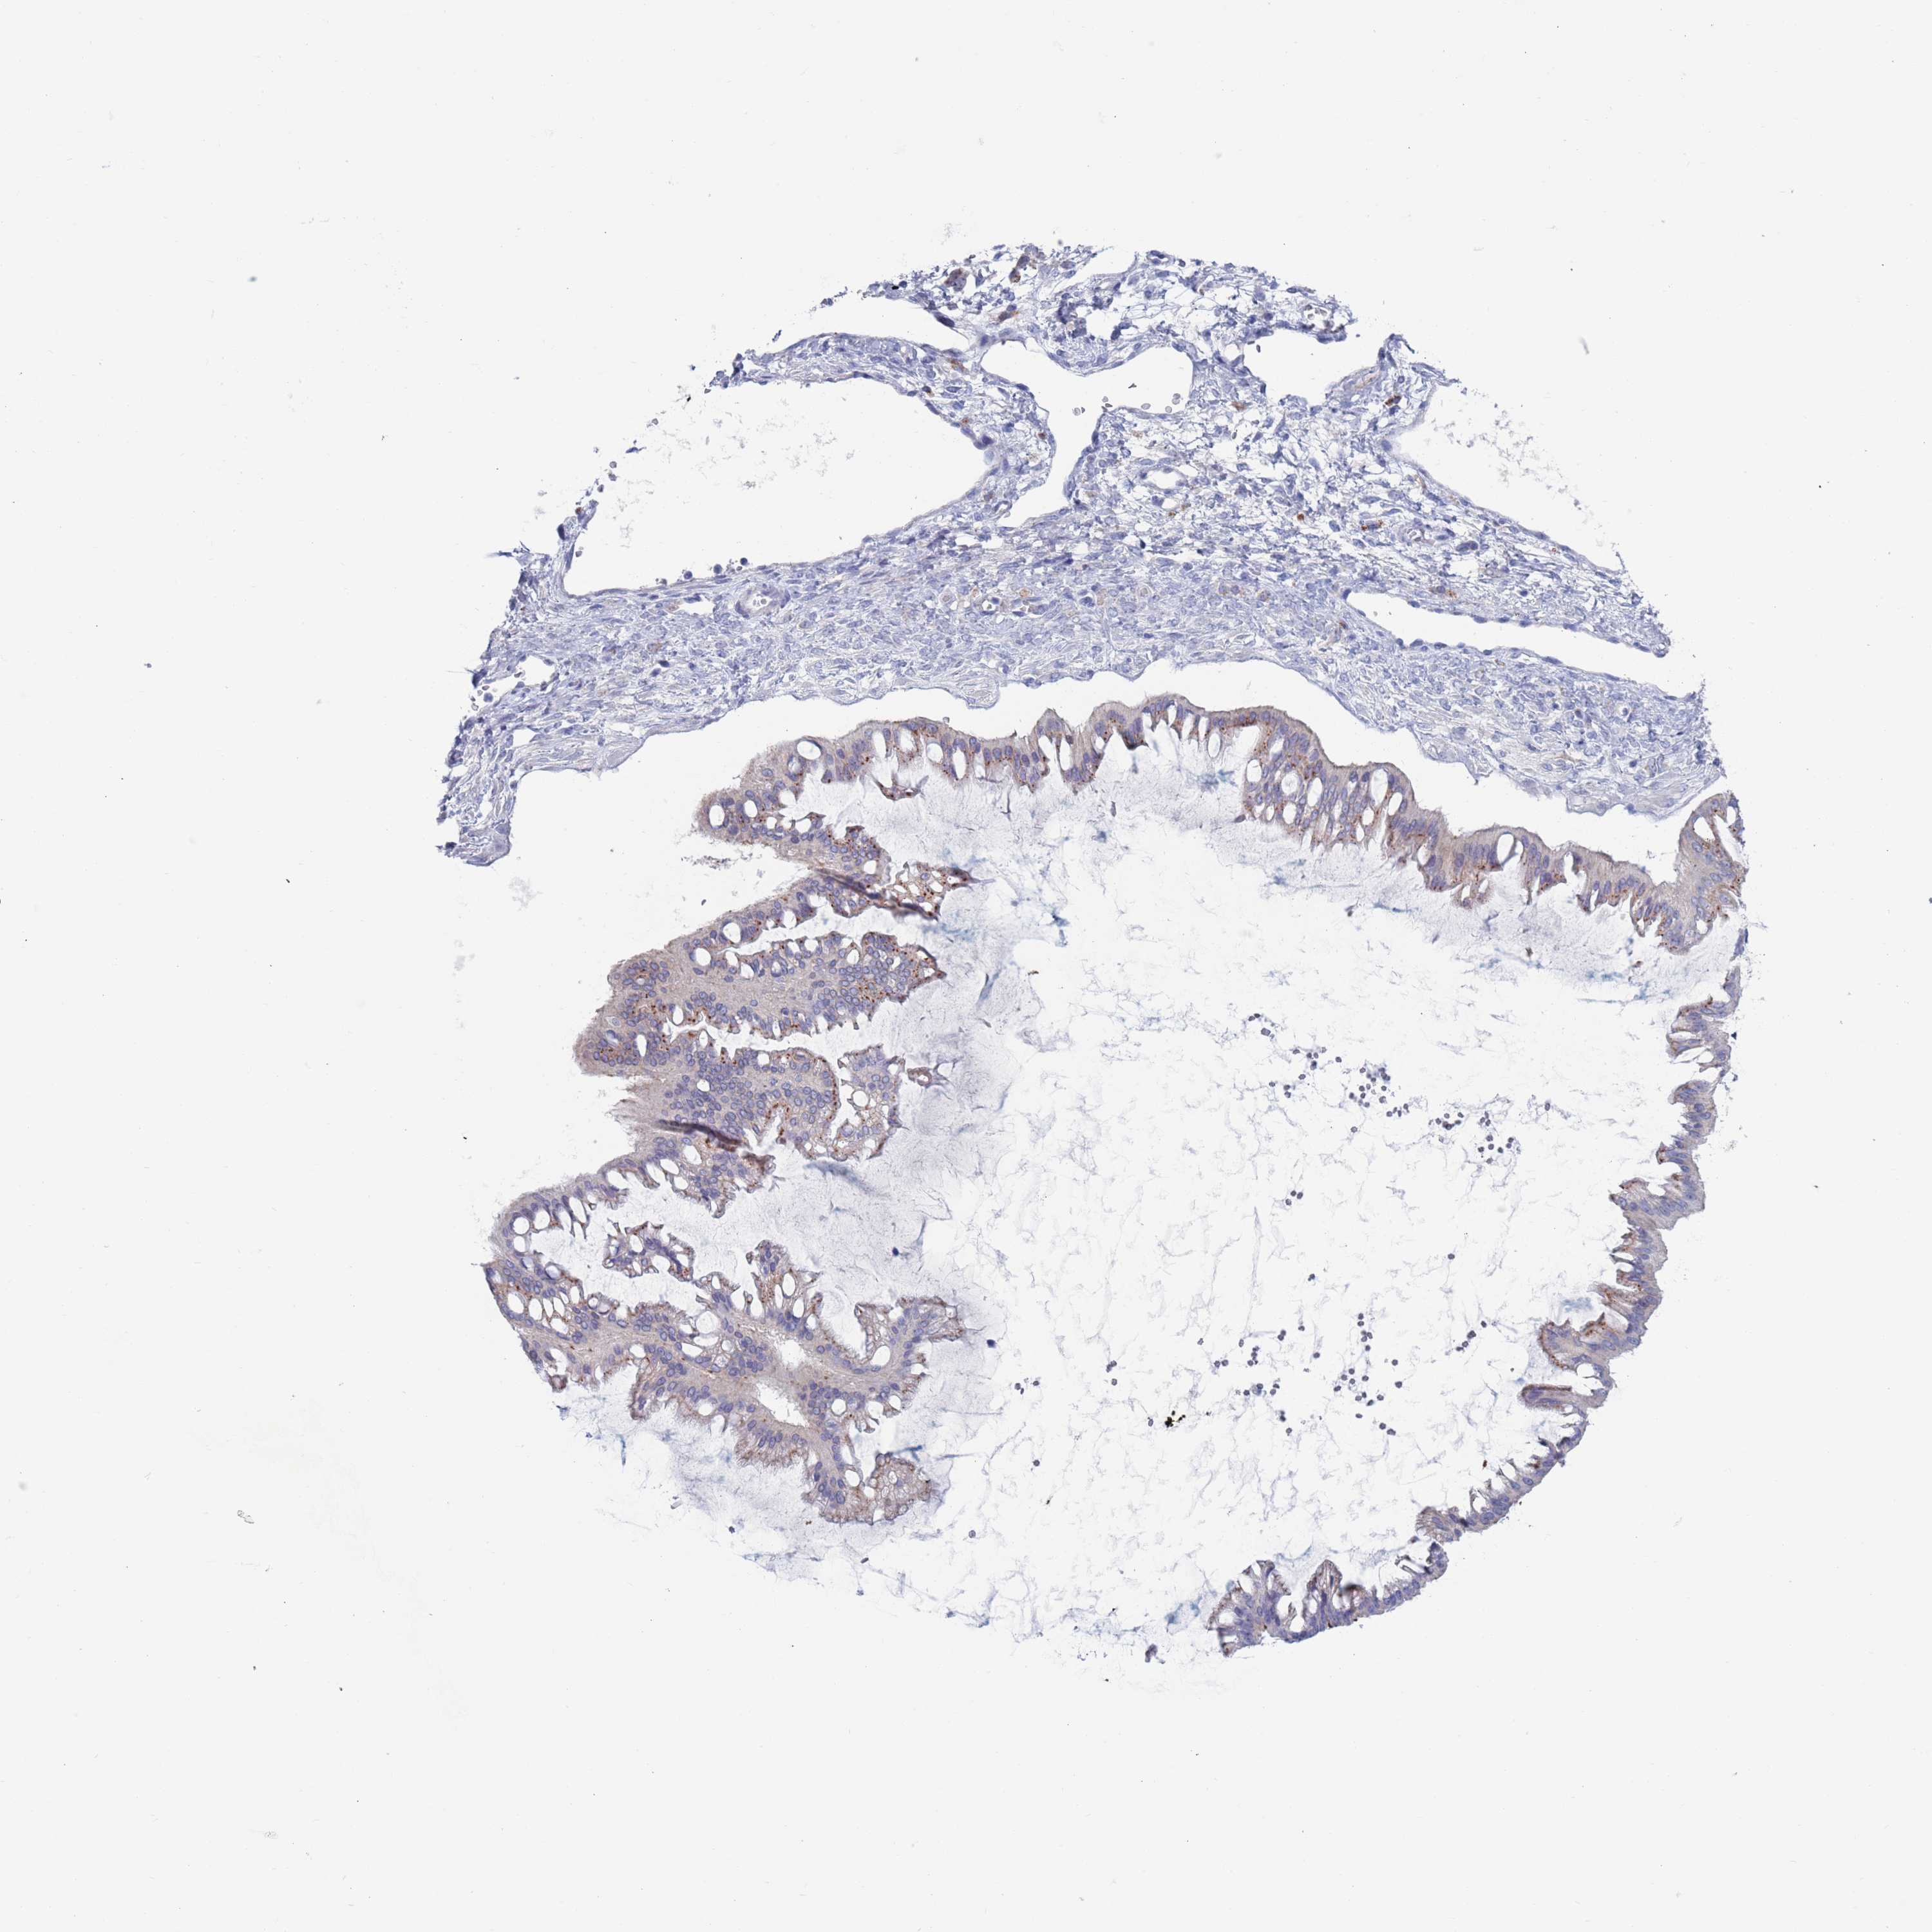

OVARIAN CANCER - Protein expressioni

A mouse-over function shows sample information and annotation data. Click on an image to view it in a full screen mode. Samples can be filtered based on level of antibody staining by selecting one or several of the following categories: high, medium, low and not detected. The assay and annotation is described here.

Note that samples used for immunohistochemistry by the Human Protein Atlas do not correspond to samples in the TCGA dataset.

Antibody stainingi

Antibody staining in the annotated cell types in the current human tissue is reported as not detected, low, medium, or high, based on conventional immunohistochemistry profiling in selected tissues. This score is based on the combination of the staining intensity and fraction of stained cells.

Each image is clickable and will lead to virtual microscopy that enables deeper exploration of all samples and also displays staining intensity scores, fraction scores and subcellular localization as well as patient and tissue information for each sample.

Antibody HPA046542

Antibody HPA056371

Staining

High

Medium

Low

Not detected

Intensity

Strong

Moderate

Weak

Negative

Quantity

>75%

75%-25%

<25%

None

Location

Nuclear

Cytoplasmic/membranous

Cytoplasmic/membranous,nuclear

Cystadenocarcinoma, serous, NOS

Carcinoma, NOS

Cystadenocarcinoma, mucinous, NOS

Carcinoma, endometroid